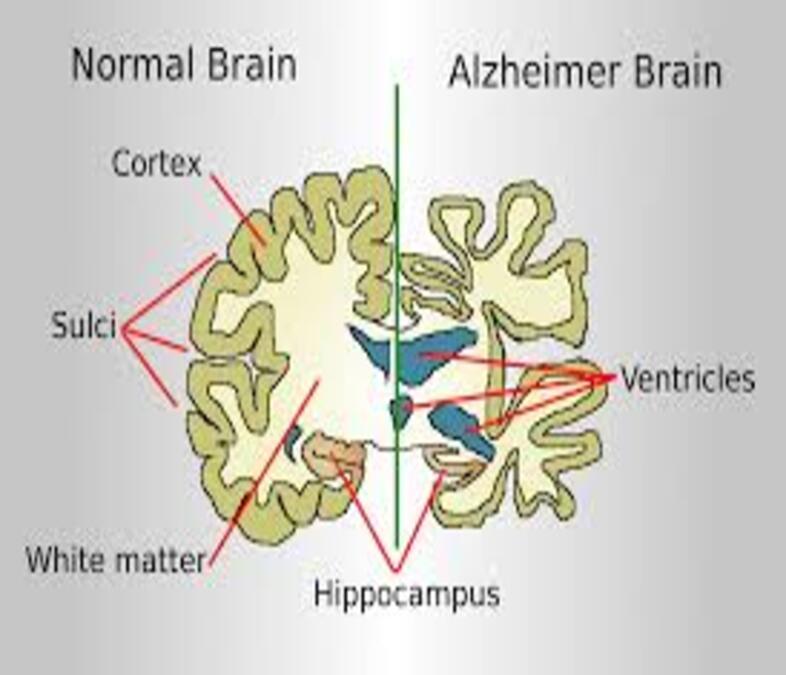

Alzheimer’s Dementia is the most common form of dementia, accounting for 60-80% of all dementia cases worldwide. While many people think of it simply as “memory loss,” Alzheimer’s Dementia is actually a complex brain disorder that affects thinking, behavior, and the ability to perform everyday activities. The disease develops when abnormal protein deposits, amyloid plaques, and tangles build up in the brain, disrupting communication between brain cells and eventually causing them to die. This process typically begins years before symptoms become noticeable, which is why early detection and understanding of Alzheimer’s Dementia is so crucial for families.

What makes Alzheimer’s Dementia particularly challenging is that it doesn’t just take away memories, it can change personality, affect judgment, and make familiar tasks feel impossible. The person you’ve known and loved is still there, but they’re experiencing the world through the filter of a changing brain.

The middle stage of Alzheimer’s Dementia often lasts the longest and requires the most significant adjustments for families. Memory loss becomes more pronounced, and your loved one might not recognize familiar faces or remember important life events. Simple tasks like getting dressed or preparing meals become challenging.

This is when families often see the biggest changes in personality and behavior. Someone who was always gentle might become agitated, or a person who loved socializing might withdraw completely. These changes aren’t choices—they’re symptoms of how Alzheimer’s Dementia affects different areas of the brain.

In the advanced stages of Alzheimer’s Dementia, verbal communication becomes limited, and your loved one will need help with all daily activities. This stage is often the most emotionally difficult for families, as the person they knew seems increasingly distant.